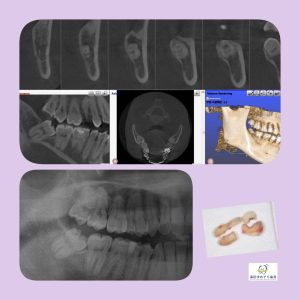

横向き親知らずの抜歯症例

院長はこのような横向きに埋まっている抜歯ケースも

1000症例以上の手術実績あり☆

横に埋まっている場合はCT撮影で安心です☆